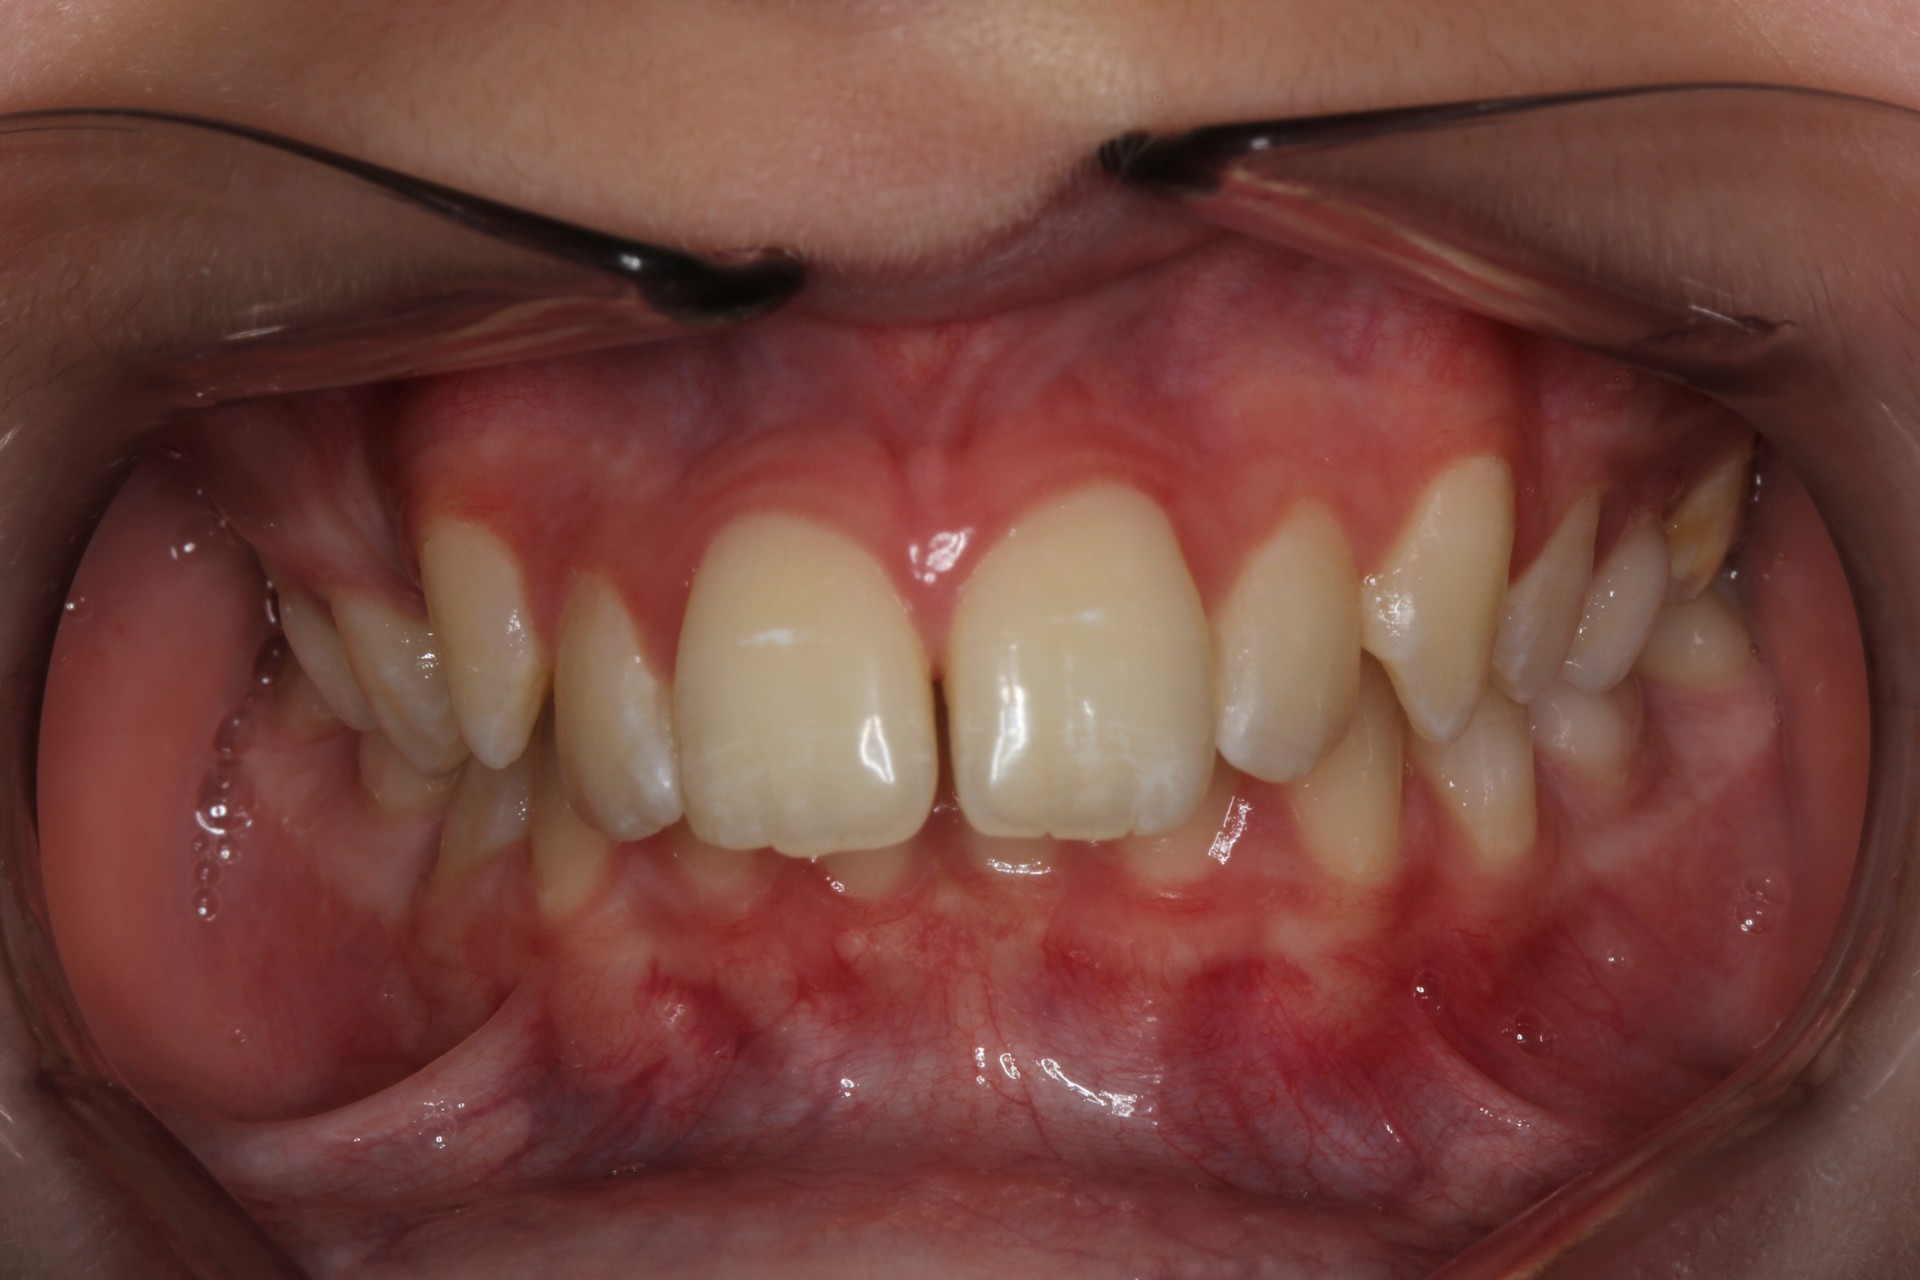

Protruding front teeth – Child case

Protruding front teeth and spacing – Child case

Protruding front teeth with midline diastema – Child case